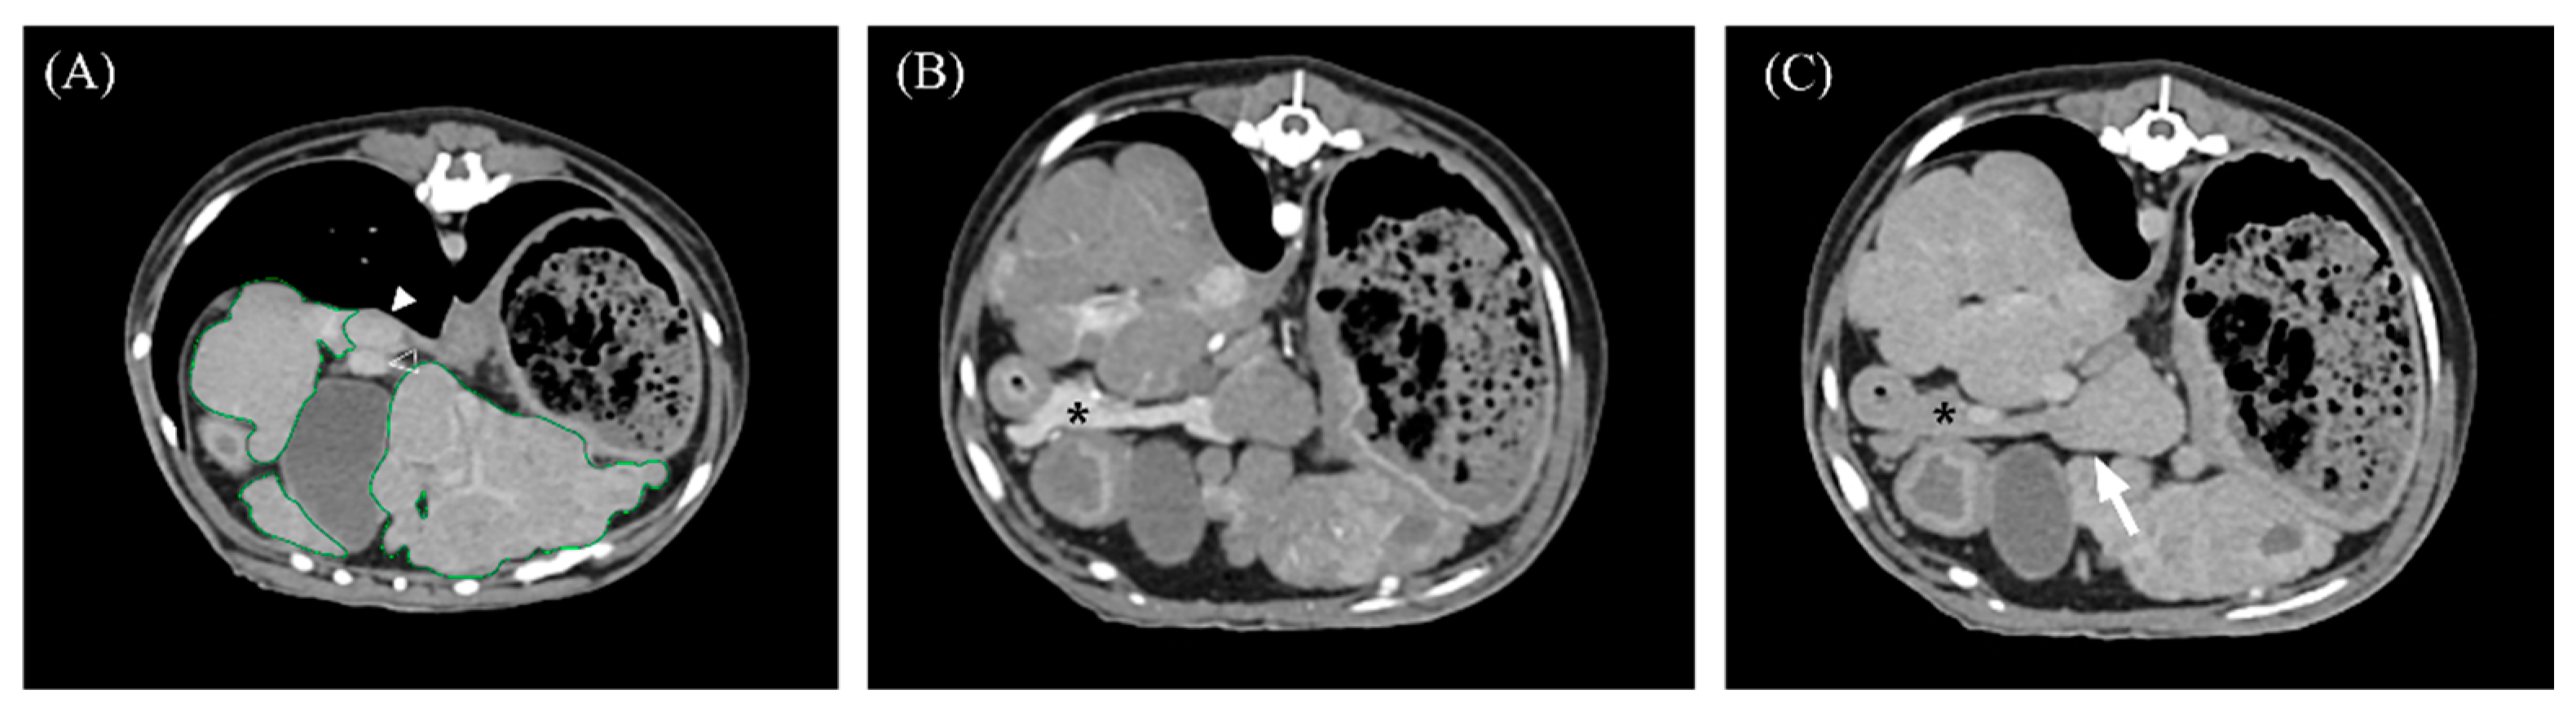

3.2. Qualitative Computed Tomographic Features

| Nodule distribution | Uniform | 13/16 (81.3%) | 8/11 (72.7%) | 5/5 (100%) | 0.509 |

| Uneven | 3/16 (18.8%) | 3/11 (27.3%) | 0/5 (0%) | ||

| Gallbladder indentation | Present | 7/16 (43.8%) | 6/11(54.5%) | 1/5 (20%) | 0.308 |

| Absent | 9/16 (56.3%) | 5/11 (45.5%) | 4/5 (80%) | ||

| Transient hepatic attenuation difference | Present | 7/13 (53.8%) | 4/8 (50%) | 3/5 (60%) | 1.000 |

| Absent | 6/13 (46.2%) | 4/8 (50%) | 2/5 (40%) |